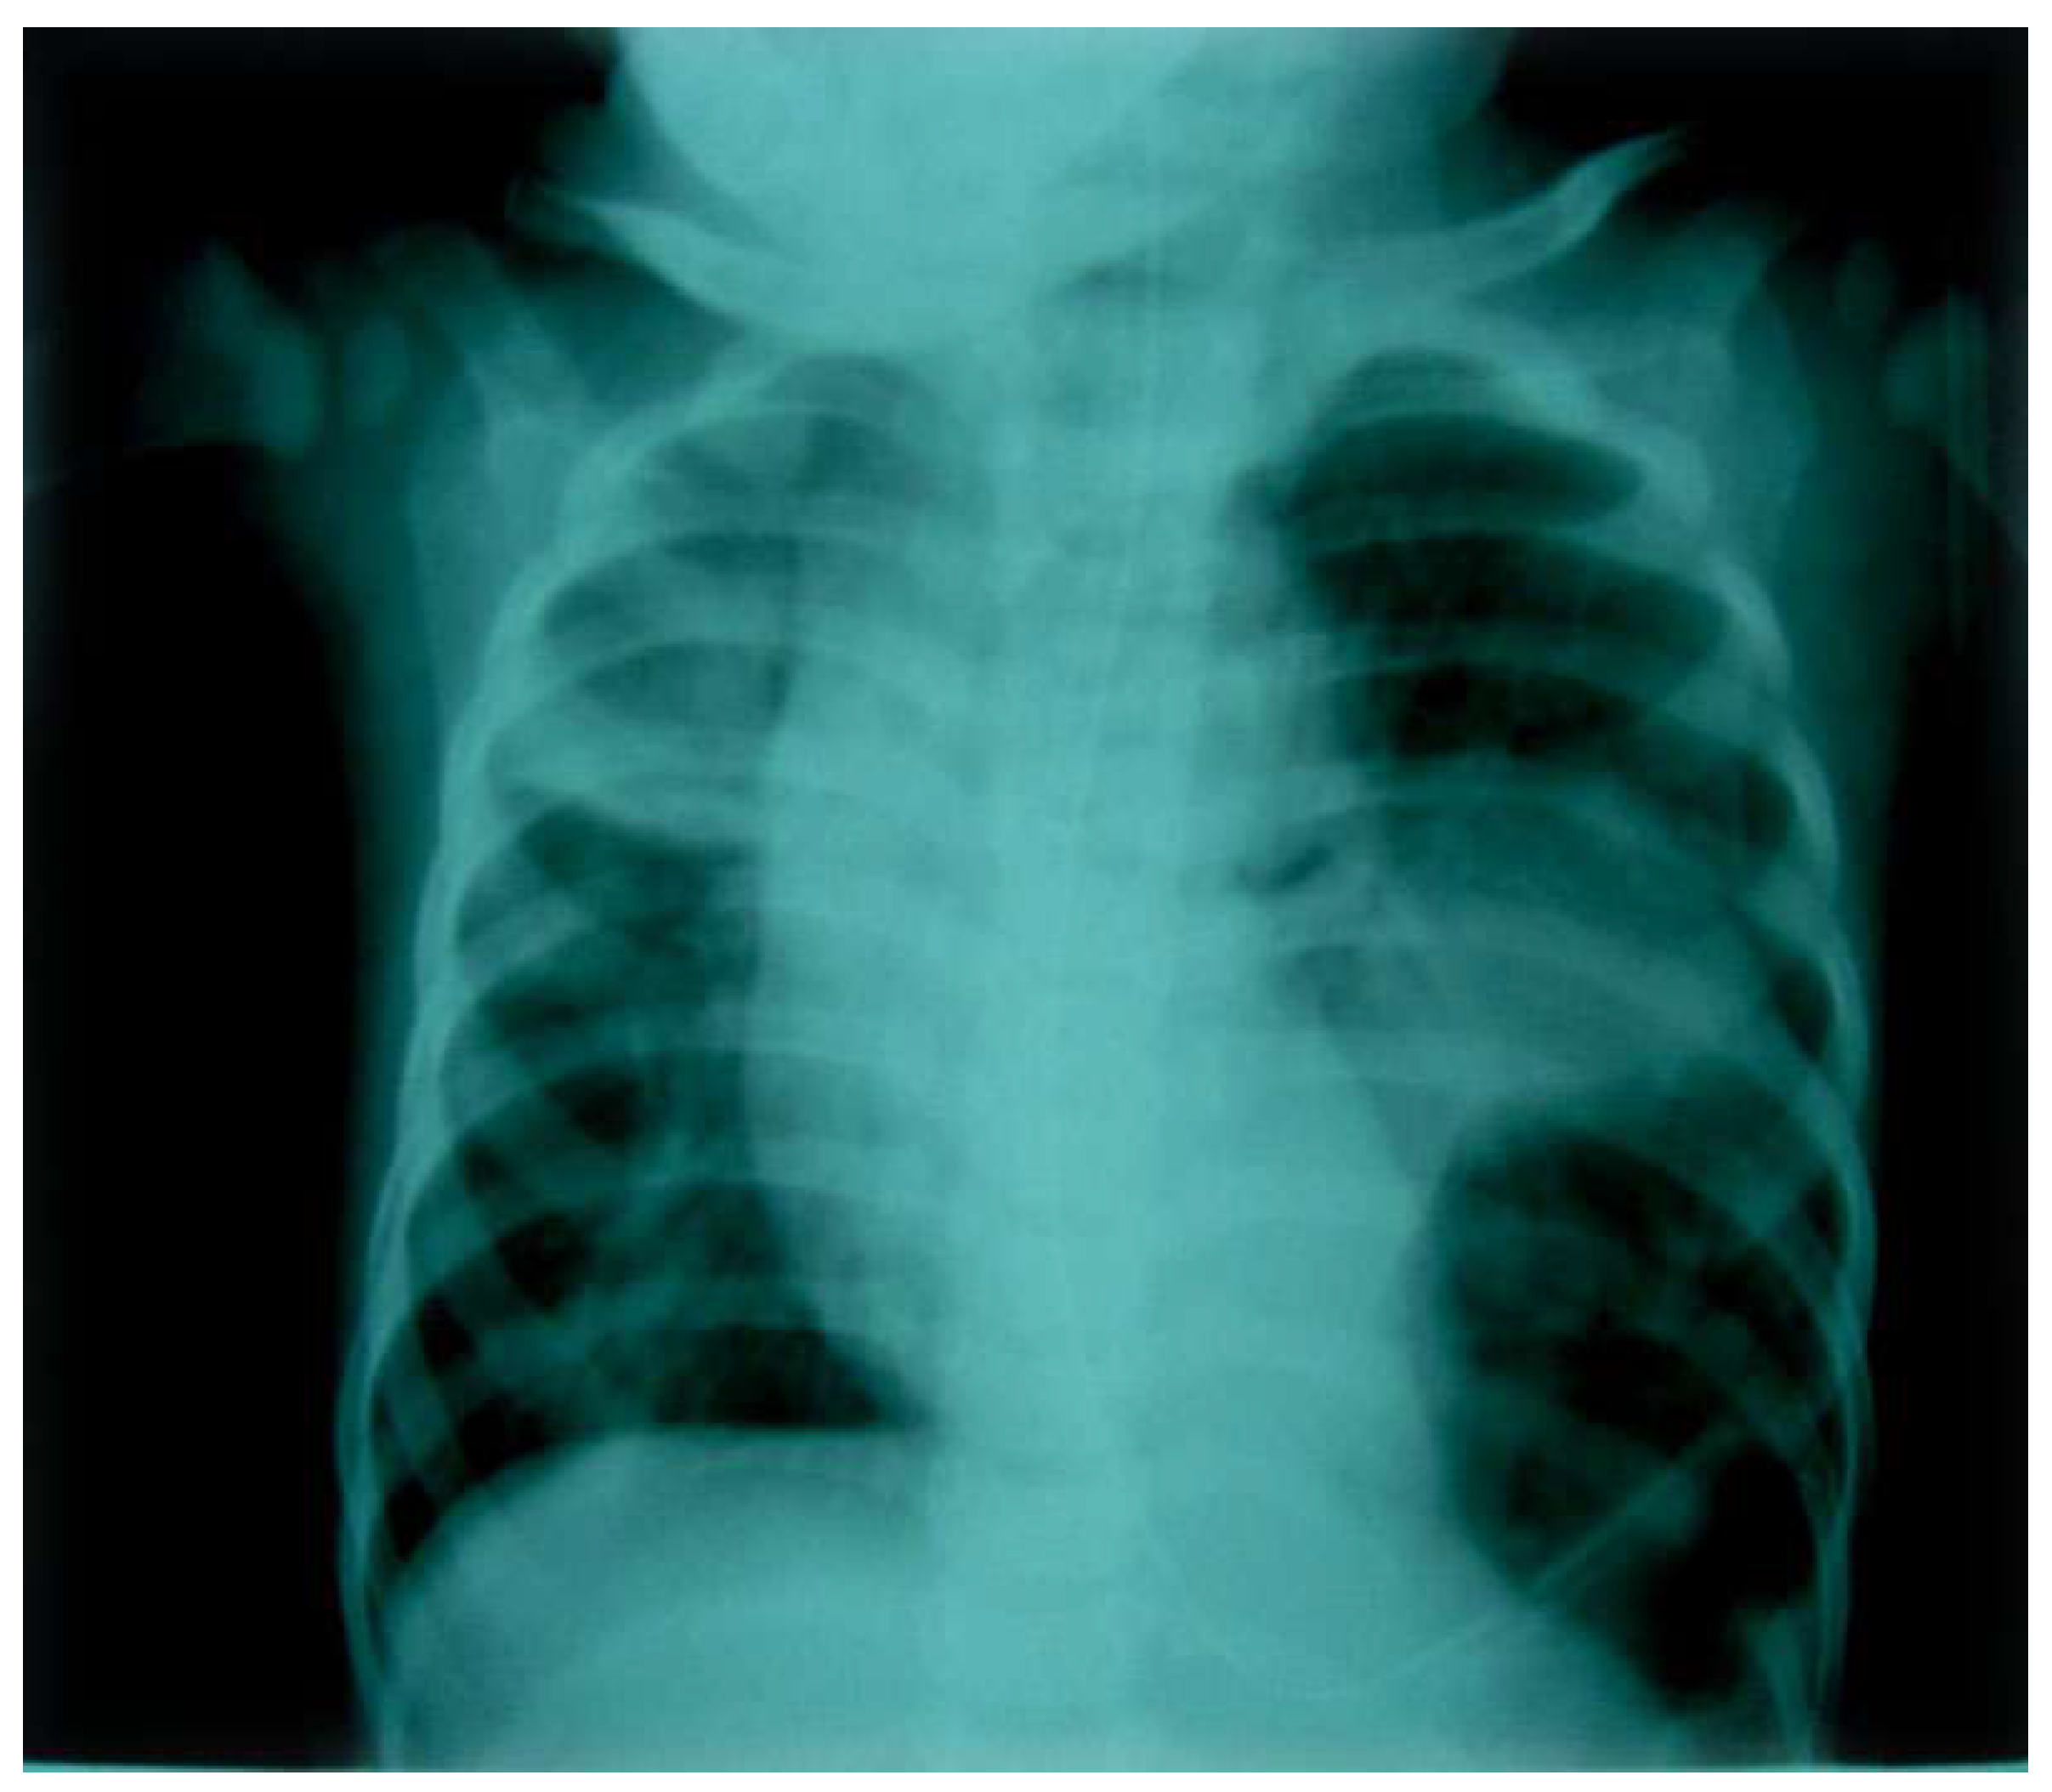

The white blood cell count was 16,000 mm3 with a differential of 84% neutrophils, 12% lymphocytes, and 4% monocytes. The patient was admitted, and oxygen was given to maintain saturation. Intravenous ampicillin was started for presumed pneumonia. She continued to have intermittent vomiting and fever. An X-ray of the chest was done and interpreted as a large left pneumothorax leading to mediastinal shift with left upper lobe consolidation (Figure 1).

Chest tube insertion was planned. Because of a clear, localized air inferiorly with an indistinct left diaphragm, a strong suspicion of diaphragmatic hernia was made, and a chest tube insertion was not attempted.

Figure 1.

Preprints 179744 g001